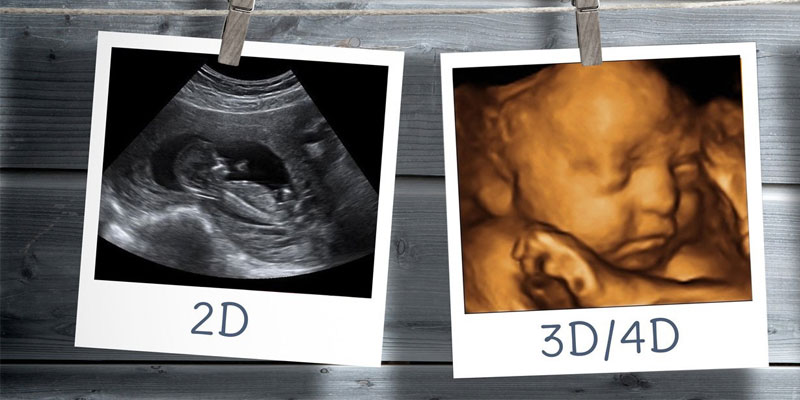

Ultra Sound

An ultrasound uses high-frequency sound waves, inaudible to humans, to create real-time images of internal body structures and organs